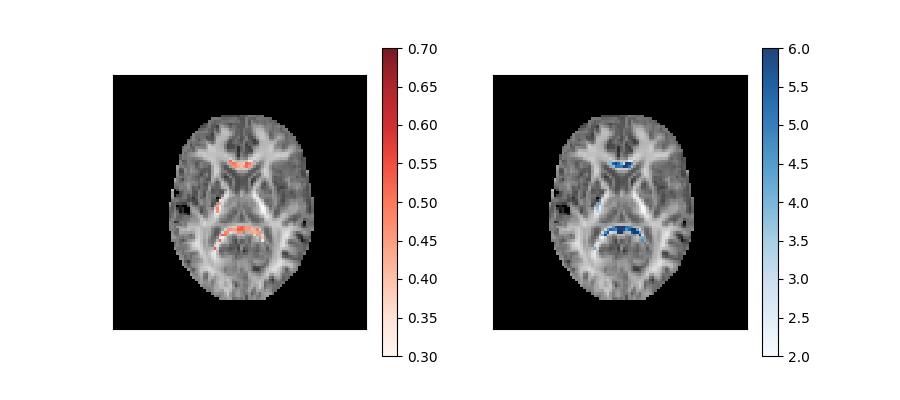

The KurtosisMicrostructureFit object created by this fit function can

then be used to extract model parameters such as the axonal water fraction

and diffusion hindered tortuosity:

These parameters are plotted below on top of the mean kurtosis maps:

Axonal water fraction (left panel) and tortuosity (right panel) values of well-aligned fiber regions overlaid on a top of a mean kurtosis all-brain image.